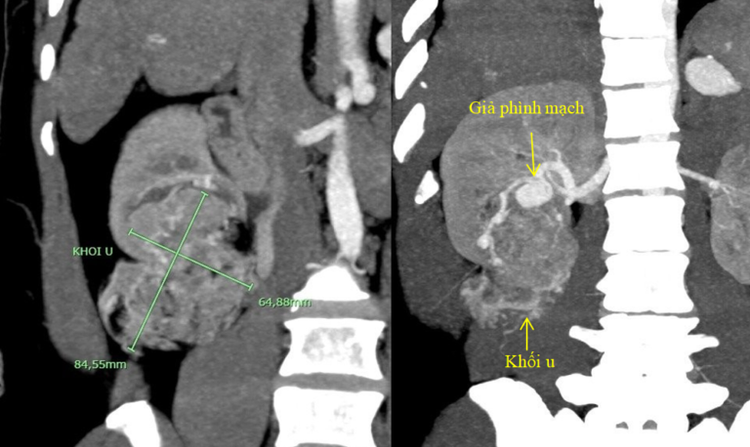

Thật bất ngờ, sau khi chụp phim, sử dụng các kỹ thuật tái tạo ảnh và dựng hình hiện đại, các bác sĩ còn phát hiện nhiều bệnh lý phối hợp bên trong ổ bụng của người bệnh, bao gồm: (1) xơ gan điển hình, (2) khối u thận phải kích thước lớn (u mạch cơ mỡ, kích thước 8,5 x 6,5 cm) và có túi giả phình nhánh động mạch thận nuôi khối u (1,9cm), và (3) khối phình động mạch lách kích thước lớn (3,0 cm).

Hình ảnh khối u thận và giả phình nhánh động mạch thận nuôi u trên phim chụp cắt lớp vi tính 128 dãy có sử dụng kỹ thuật tái tạo và dựng hình đa bình diệnHình ảnh khối u thận và giả phình nhánh động mạch thận nuôi u trên phim chụp cắt lớp vi tính 128 dãy có sử dụng kỹ thuật tái tạo và dựng hình đa bình diện